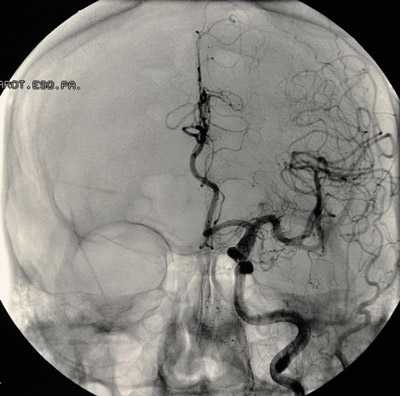

Хирургическая тактика использования временного клипирования приводящего (-их) артериального (-ых) сосуда (-ов) коллегиально обсуждалась в каждом конкретном случае предстоящего нейрохирургического вмешательства на основании заключения нейрохирургического диагностического комплекса: МРТ, КТ головного мозга, КТ-ангиографии сосудов головного мозга, осмотра неврологом и нейрохирургами. Анестезиолог участвовал в обсуждении больных. Общая характеристика пациентов представлена в табл. 1. Таблица 1. Общая характеристика больных Примечание. ГБ — гипертоническая болезнь, ФП — фибрилляция предсердий; ЯБДК — язвенная болезнь двенадцатиперстной кишки.

Операция заключалась в проведении костнопластической трепанации черепа, широком раскрытии базальных цистерн с аспирацией ликвора, что позволяло уменьшить мозг в объеме и улучшить доступ к артериям основания мозга. Используя операционный микроскоп и микрохирургическую технику, выделяли вначале несущую артерию, затем по возможности одну или две отводящие артерии. В случае интраоперационного разрыва аневризмы это позволяло осуществить наложение временных клипс. Микрохирургическую операцию проводили с превентивным временным клипированием приводящего сосуда, на питающую аневризму артерию накладывали временную клипсу с короткими интервалами окклюзии сосуда. В некоторых случаях анатомические условия позволяли оперирующему нейрохирургу принять решение о клипировании шейки аневризмы без выполнения временной окклюзии питающего сосуда.

Г. А. Асатуряном и соавт. [10, 11] было установлено, что максимальное снижение ЛМК регистрируется при временном клипировании СМА — до 14 мл/100 г/мин, при временном клипировании ВСА ЛМК снижается до 18 мл/100 г/мин, при временном клипировании ПМА — до 39 мл/100 г/мин. Однако лакунарные инфаркты мозга после операций с применением временного клипирования, по данным КТ, выполненной после операции, чаще регистрируют в бассейнах базилярной артерии (БА) и СМА в зонах кровоснабжения отходящих от них перфорирующих ветвей — в базальных ганглиях и таламусе. Поддержание коллатерального кровообращения на адекватном уровне обеспечивается механизмом ауторегуляции мозгового кровотока (АМК). Во всех случаях нарушения АМК мозговой кровоток становится напрямую зависим от системного АД, а коллатеральное кровообращение в бассейне окклюзированной артерии неэффективно [12]. В.В. Крылов и соавт. [6, 13] показали, что применение временного клипирования во время оперативного вмешательства в остром периоде субарахноидального кровоизлияния (САК) чаще, чем в «холодном» периоде, приводит к развитию локальной ишемии головного мозга, а тяжесть состояния больного в остром периоде разрыва ЦА, уровень внутричерепного давления и выраженность церебрального ангиоспазма коррелируют с послеоперационной летальностью. Данная закономерность связана с морфологическими изменениями стенки сосудов, происходящими после САК [14]. Под влиянием воздействия агрессивной среды, в которую попадает сосуд после геморрагии, наступает другое качественное состояние артерии, которое изменяет просвет сосуда: к явлениям констрикции (спазма) присоединяются явления стеноза, развивается констриктивно-стенотическая артериопатия [6]. Констриктивно-стенотическая артериопатия (так называемый вазоспазм) включает такие процессы, как повреждение эндотелия, отек, дезорганизация соединительной ткани, контрактурная дегенерация гладкомышечных клеток, что не позволяет сосуду спонтанно вернуться в нормальное состояние. Установлено, что на 11—24-е сутки после САК в суженном просвете артерии выявляются пристеночные тромбы с признаками лизиса. В условиях необратимой артериопатии наложение клипсы на сосуд может усугублять локальную церебральную ишемию, которая не разрешается даже после удаления съемного клипса [14]. Риск ишемических осложнений повышен у пациентов в стадии суб- и декомпенсации (III—V степени по шкале Hunt—Hess), у которых наиболее часто обнаруживаются констриктивно-стенотическая артериопатия и нарушение ауторегуляторных механизмов мозгового кровообращения [12, 15].

аневризма сосудов мозга на снимке

Перед планированием операции больной подвергается всевозможным обследованиям, включая анализы крови, мочи, коагулограмму, кардиограмму и т. д., как и при других оперативных вмешательствах. Для локализации и уточнения характера сосудистого образования проводят КТ, МРТ с контрастированием, ангиографию, ультразвуковое исследование с допплером.